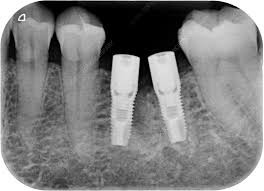

ایمپلنت روشی جدید و کارآمد است در این روش دندان های آسیب دیده، شکسته شده یا گم شده را به طور کاملا از دهان بیرون می آورند و با استفاده از جراحی، دندان های مصنوعی را با پایه فلزی به جای دندان آسیب دیده، شکسته شده یا گم شده قرار می دهند. این دندان های مصنوعی که با پایه فلزی در دهان کاشته می شوند بسیار شبیه نمونه دندان های واقعی عمل می کنند. این دندان ها کاملا محکم و قوی هستند. پایه فلزی دندان های مصنوعی معمولا از جنس تیتانیوم (titanium) است.

پیچی که در فک شما کاشته می شود به عنوان جایگزین ریشه دندان شما است. جراح دندان پس از ترمیم استخوان های اطراف محل ایمپلنت ، دندان مصنوعی را در جای خود قرار می دهد که با استخوان ها اطراف محکم در جای خود نگه داشته می شوند. ایمپلنت دندان جلوه زیبایی را به لبخند شما می بخشد. ایمپلنت کردن به شما این اعتماد به نفس را خواهد داد تا به راحتی غذا میل کنید، صحبت کنید و بدون هیچ نگرانی کار هایی را که با دندان طبیعی انجام میداید با دندان های ایمپلنت نیز انجام دهید.

3. جراحی ایمپلنت دندان: پس از کشیدن دندان توسط پزشک نوبت به قرار دادن ایمپلنت تیتانیومی (titanium) (قرار دادن پایه فلزی در لثه) به جای دندانی که قبل کشیده شده است، می رسد. جراحی ایمپلنت دندان به مدت 1 الی 2 ساعت طول می کشد و پس از جراحی ایمپلنت دندان شما برای بهبودی فک بالا و پایین حدودا به مدت 7 ماه نیاز دارید همچنین در اواخر ماه هفتم پزشک یک قطعه فلزی گرد را به مدت 2 هفته روی پایه فلزی قرار می دهد تا لثه از ایمپلنت دور بماند.

4. اباتمنت: بعد از جراحی ایمپلنت دندان نوبت به اباتمنت می رسد که نگهدارنده تاج همیشگی است. ابتدا پزشک قطعه گرد را بر می دارد و سپس اباتمنت را روی پایه تیتانیومی (titanium) قرار می دهد. بر روی اباتمنت تاج موقتی را برای تست بر روی اباتمنت قرار می دهند که حدودا به مدت 5/1 ماه طول می کشد.